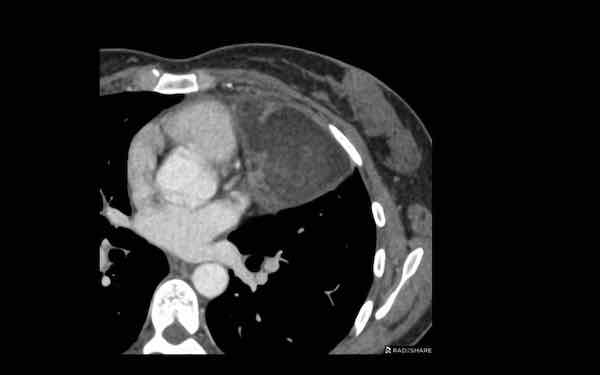

U lympho

Các hình ảnh này của một bệnh nhân nữ 60 tuổi.

Bệnh nhân có rối loạn nhịp tim và phát hiện tình cờ một khối trên CT ngực.

Hình ảnh

Khối có tỷ trọng cao trên phim chụp sau tiêm thuốc cản quang.

Không có mỡ đại thể.

Bờ hơi không đều.

Và có một khối thứ hai (mũi tên). Trên các lớp cắt khác còn thấy thêm nhiều khối nữa.

Thảo luận

Khi có nhiều khối, chẩn đoán có khả năng nhất là u lympho.

Bất cứ khi nào u lympho nằm trong chẩn đoán phân biệt, cần phải lấy mẫu mô và bắt đầu hóa trị ngay khi xác định được loại u lympho.